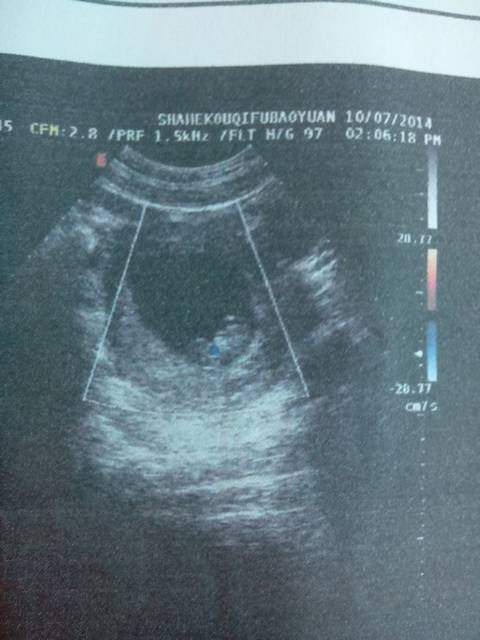

宝妈们,你们看得到我的宝宝了没? 宝妈们,你们看得到我的宝宝了没? 点击展开 傻瓜♀不弃↗旭 2014-07-10 20:20 为您推荐: 其他回答 你好,这个时候胎儿还很小的哦,看的不是很清晰的哦,平时的时候宝妈多注意些, 一般4个月左右的时候可以看清的 斑驳的流年88 2014-07-12 15:44 还好吧,我也不太懂,小你就多吃点营养嘛,这又没有关系的 溺丶祂海 2014-07-11 06:41 看到了。宝妈几周 爱源哥得永生 2014-07-10 22:29 看到了啊,蓝蓝那里,你几个月啊 溺丶祂海 2014-07-10 20:31 相关问题 我想问一下各位宝妈,生气宝宝就会没有母乳吃吗 远嫁的宝妈都过得好吗?生宝宝娘家的人都没有一个人来看我、结婚的时候也没有一个人来看我、妈妈65岁了 在等宝宝起来喝奶奶,我怕我刚睡了宝宝就醒了,我又不想起来了,有没有宝妈像我这样子的